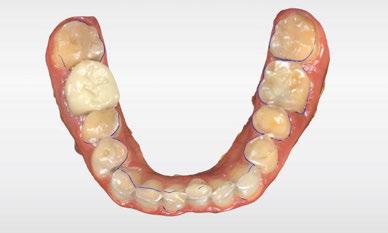

Terminada esta fase se elaboró una propuesta de diseño (CEREC,

SW 5.2, Dentsply Sirona) (Figuras 22-27), la cual fue materializada en dos tipos de materiales a partir de bloques cerámicos IPS Empress CAD y cerámica vítrea de disilicato de litio IPS E.max CAD (Figuras 28-30)

Figura 6. Impresión digital, vista oclusal, maxilar inferior.

Figura 7. Modelado digital. Figura 9. Propuesta de diseño en oclusión Figura 10. Vista lateral derecha. Figura 8. Propuesta de diseño arcada superior. Figura 11. Vista oclusal superior del modelado. Figura 12. Mock Up impreso en oclusión. Figura 14. Mock Up que evidencia el desgaste dentario en el maxilar inferior.